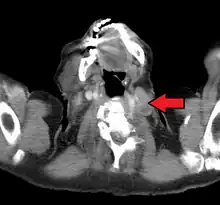

El nódulo de Virchow, visto en una tomografía computarizada.